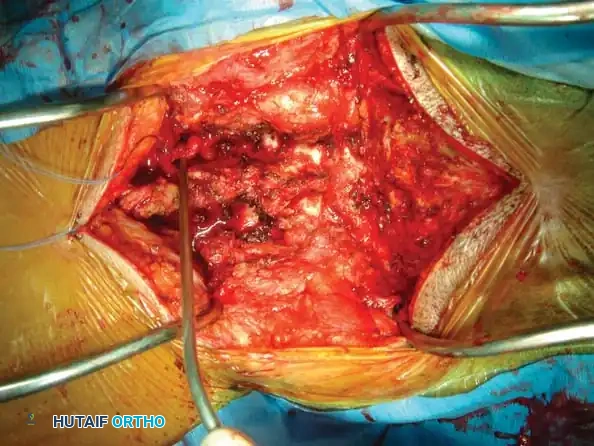

Anterior Cervical Discectomy and Fusion (ACDF)

Indications: Anterior column compromise, extruded traumatic disc herniations, or as the first stage in a 360-degree fusion for severe distractive flexion injuries.

Positioning & Approach:

* The patient is positioned supine on a radiolucent Jackson table.

* The neck is maintained in neutral alignment using Gardner-Wells tongs with 5-10 lbs of maintenance traction.

* A standard Smith-Robinson transverse incision is made, typically left-sided to avoid the recurrent laryngeal nerve (which has a more predictable course on the left).

* The avascular plane between the visceral axis (trachea/esophagus) medially and the carotid sheath laterally is developed.

Surgical Steps:

1. Exposure: Retract the longus colli muscles laterally to expose the anterior vertebral bodies and the damaged disc space.

2. Discectomy: Perform a complete discectomy using curettes and pituitary rongeurs. In trauma, the PLL is often torn; carefully remove any extruded disc fragments compressing the cord.

3. Endplate Preparation: Decorticate the cartilaginous endplates using a high-speed burr to expose bleeding subchondral bone, ensuring a robust fusion bed.

4. Grafting: Insert a structural allograft or PEEK cage packed with autograft/demineralized bone matrix (DBM) into the disc space.

5. Plating: Apply a rigid anterior cervical plate. Ensure screws are placed parallel to the endplates and do not breach the adjacent disc spaces.

Fig 6. Anterior cervical plating construct providing rigid stabilization of the anterior column.